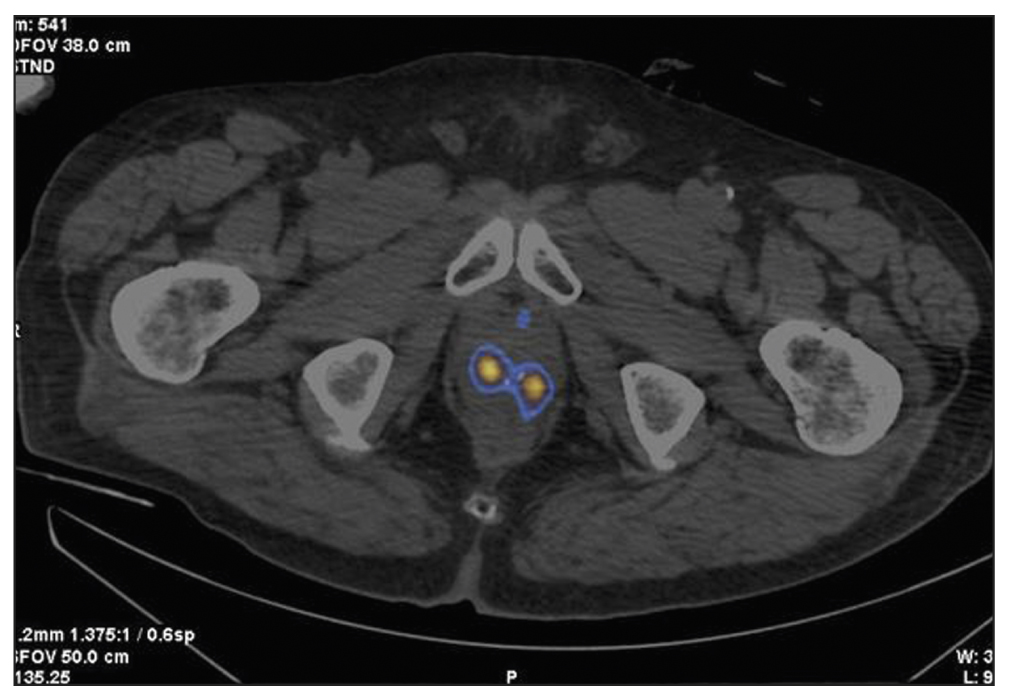

Patient Z., 79 years old, was admitted with diffuse prostatic hyperplasia. PSA level was 4.5 ng/mL. No abnormal lesions were found in the prostate tissue using ultrasound, TRUS, and contrast-enhanced MRI. SPECT/CT with 99mTc-HYNIC-PSMA revealed 15-mm3 sites of RP accumulation in the prostate tissue (Figure 3). Because rectal amputation made US-guided prostate biopsy impossible, a targeted CT-guided biopsy was performed pararectally. A morphological diagnosis was adenocarcinoma, Gleason 6 (3 + 3).

Fig. 3. Patient Z., 7 years old, SPECT/CT with 99mTc-HYNIC-PSMA: Sites of radiopharmaceutical accumulation in transitory zones of both lobes at the border of the middle third and the apex of the prostate gland.

In this case, two problems were revealed: an unknown cause of increased PSA over time and the inability to perform a targeted prostate carcinoma biopsy under US guide. Both problems were successfully resolved using hybrid SPECT/CT with 99mTc-HYNIC-PSMA followed by CT-guided RP accumulation site biopsy, and precision brachytherapy was performed with a smaller number of 125I microsources due to the SPECT/CT pattern.